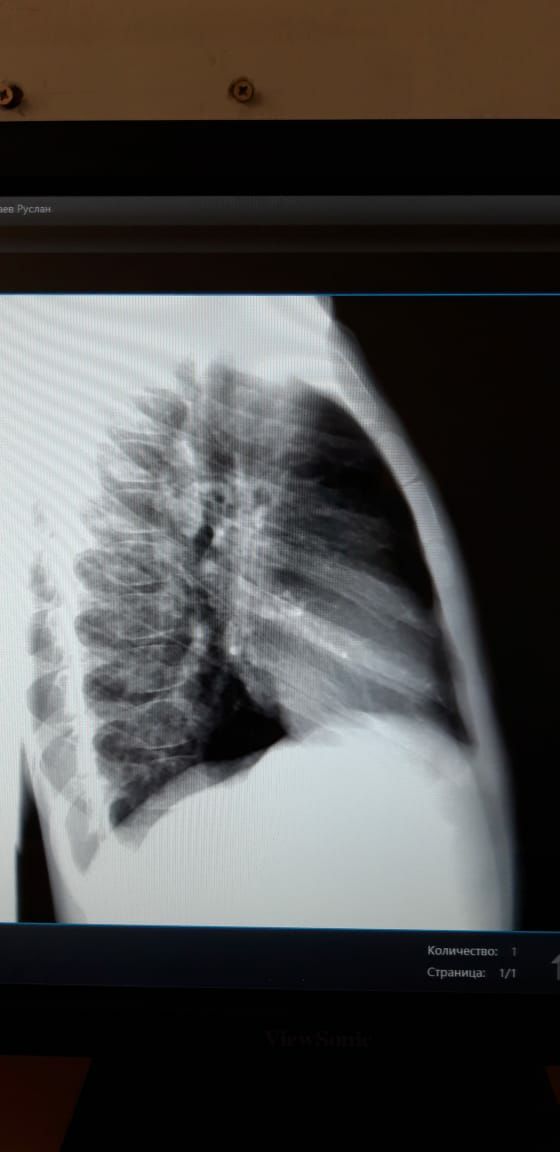

Здравствуйте ув. Коллеги! Посмотрите снимки ребенка мальчика 2016г. В крови от 5 июля-45 СОЭ. Неделю назад температурил. Сейчвс педиатр ставит ОРИ...Обследование... мы с Белой  Солт.решили что там с / долевая пневмония справа.....но никто кроме меня не видит овоидную тень  в С1-2?...я понимаю по этим снимкам трудно судить...но я сделала несколько с разной интенсивностью снимков... пожалуйста кто  что может посоветовать....мы решили пролечить и контроль...

Фото от 777